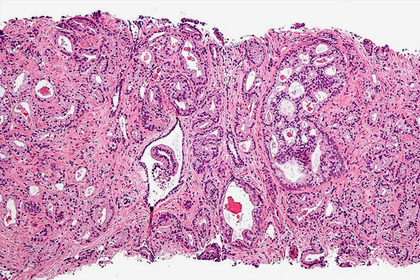

Ученые Университета Кардиффа (Великобритания) обнаружили мутацию, которая способствует развитию агрессивной формы злокачественных опухолей, называемой кастрационно-резистентным раком предстательной железы. Об этом сообщается в пресс-релизе на MedicaXpress.

Исследователи выяснили, что мутация, затрагивающая ген PIK3CA в клетках предстательной железы, способствует развитию агрессивной формы новообразования. PIK3CA кодирует белок, являющийся субъединицей фермента фосфоинозитид-3-киназы (PI3K), участвующего в процессе роста, деления клеток и их ухода от апоптоза (программируемой клеточной гибели). Другой ген PTEN отвечает за блокирование активности PI3K, и мутации в нем также вызывают развитие опухолей.